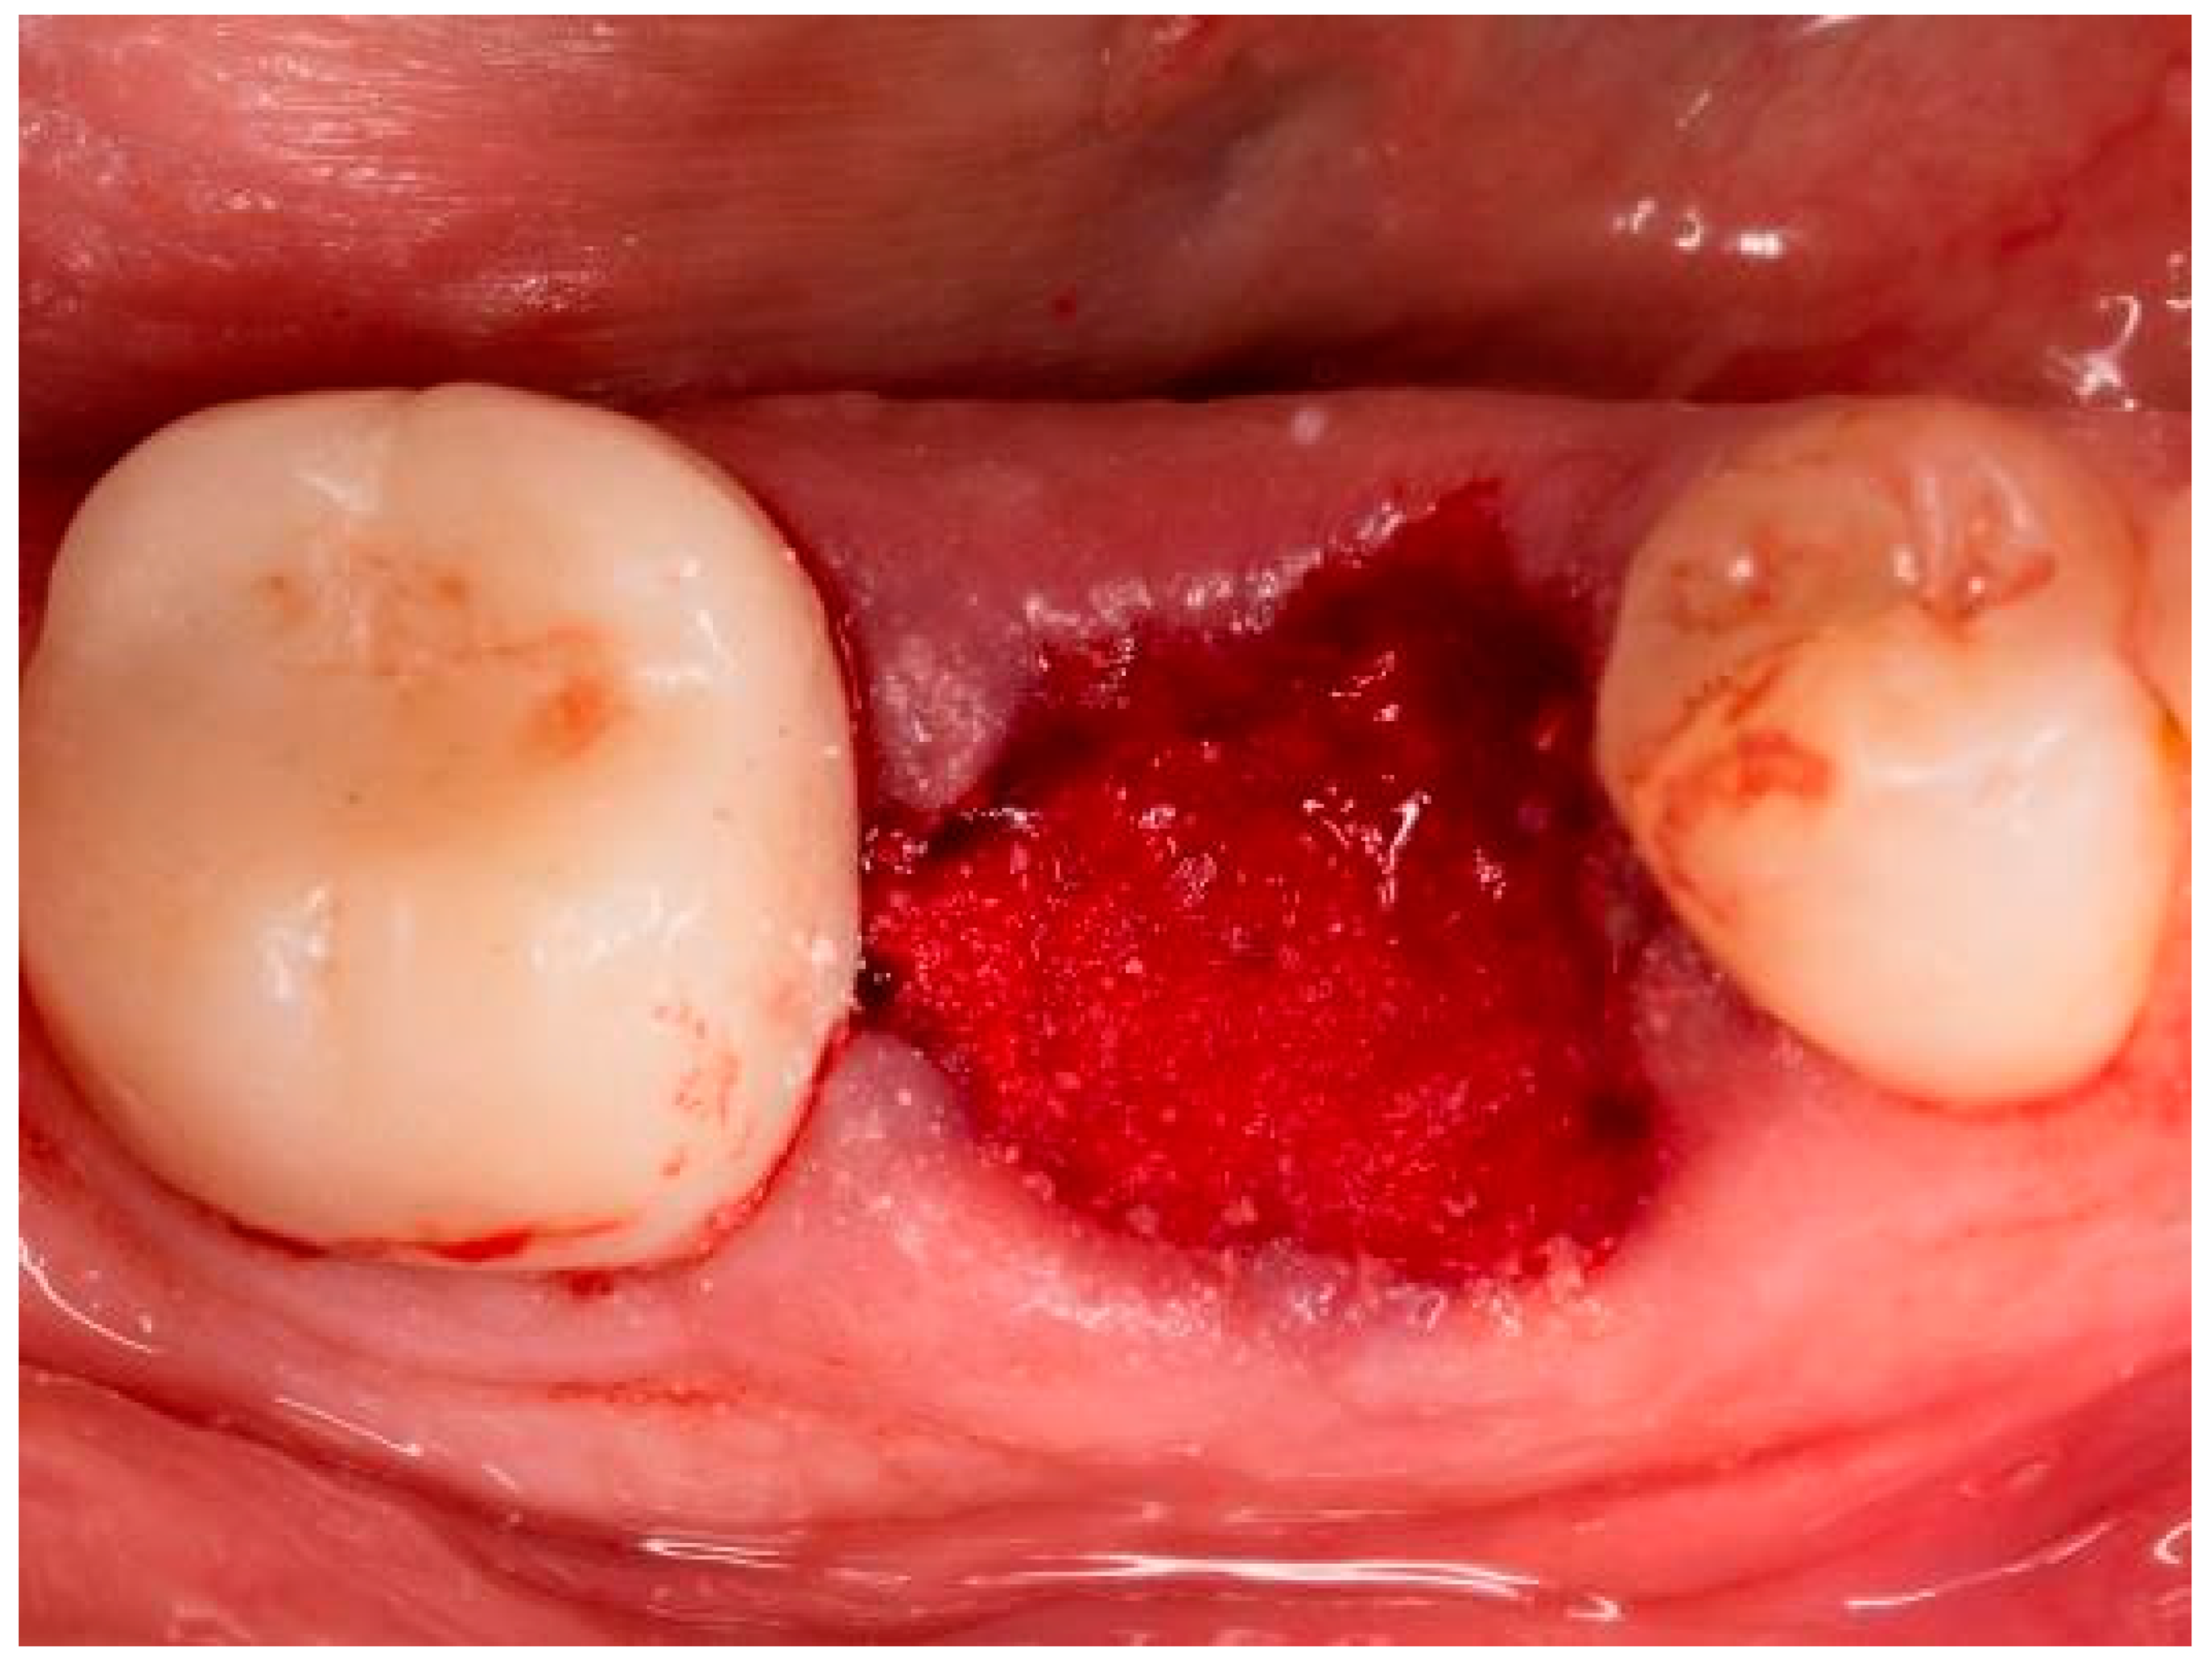

2. Materials and Methods